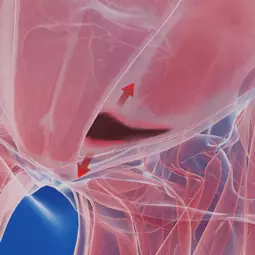

Športnikova kila je izraz za bolečinski sindrom v dimljah, ki je precej kompleksen tako glede diagnostike, kot samega zdravljenja.

Razlogov za bolečino v dimljah je veliko, lahko gre za pravo kilo, ki se vidi kot izboklina iz trebuha ob napenjanju, pogosti vzroki so lahko okvare hrbtenice, pri katerih bolečina pasasto seva v dimlja, možni pa so tudi razni urološki vzroki.